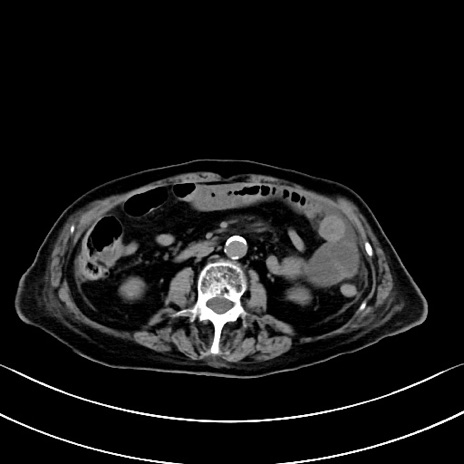

横断像

他院CT